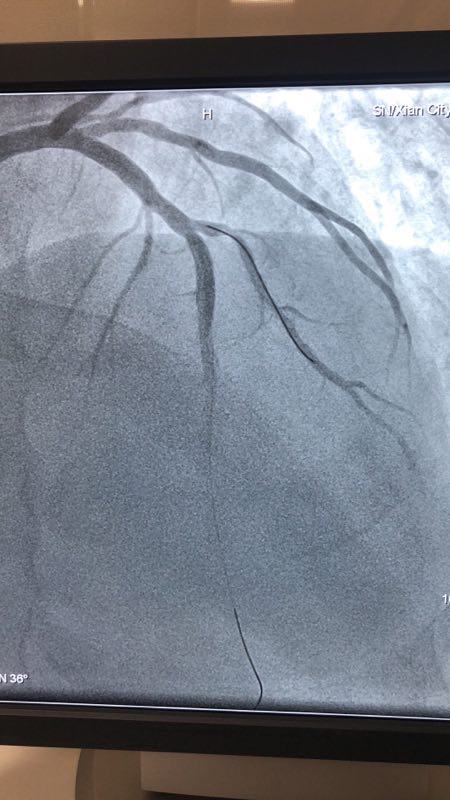

此例患者,男性,56岁,11年前因心绞痛在西京成人导航 行冠状动脉造影检查后于D1对角支置入1枚支架治疗。术后患者口服“阿司匹林肠溶片、氯吡格雷、阿托伐他汀”等药物治疗1年后自行停药,并有长期大量吸烟史。2018年12月24日患者突发胸痛、胸闷,急来成人导航就诊。急诊行冠状动脉造影检查提示D1对角支原支架内再狭窄70%-90%。急救中心主任张誉洋副主任医师考虑到第一对角支管径较小,于原支架内再次置入支架引起再狭窄的风险极大,遂建议应用药物涂层球囊扩张术治疗D1对角支原支架内狭窄。与患者充分沟通后,于12月27日行冠脉药物涂层球囊PTCA术治疗,造影显示血管开通情况良好,术后患者症状明显改善。